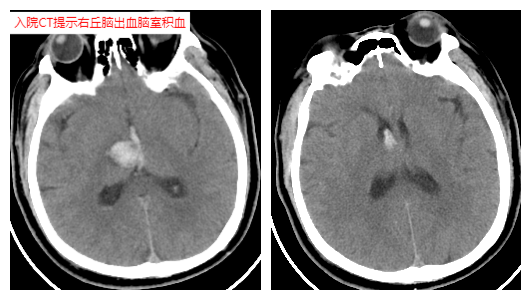

該患者最初因腦出血入住本地其他醫(yī)院,次日清晨突發(fā)心跳停止,經(jīng)心肺復(fù)蘇后緊急轉(zhuǎn)入隨州市中心醫(yī)院ICU。當(dāng)時患者瞳孔散大、呼吸衰竭、血壓極低,必須依靠大量藥物維持,CT顯示腦部出血加重,生命岌岌可危。

在這生死關(guān)頭,神經(jīng)外科團隊迅速評估后作出關(guān)鍵決定:立即進行腦部引流手術(shù),緩解顱內(nèi)壓力。盡管患者當(dāng)時生命體征極不穩(wěn)定,手術(shù)風(fēng)險巨大,但為了爭取一線生機,醫(yī)療團隊毅然決定頂壓而上。